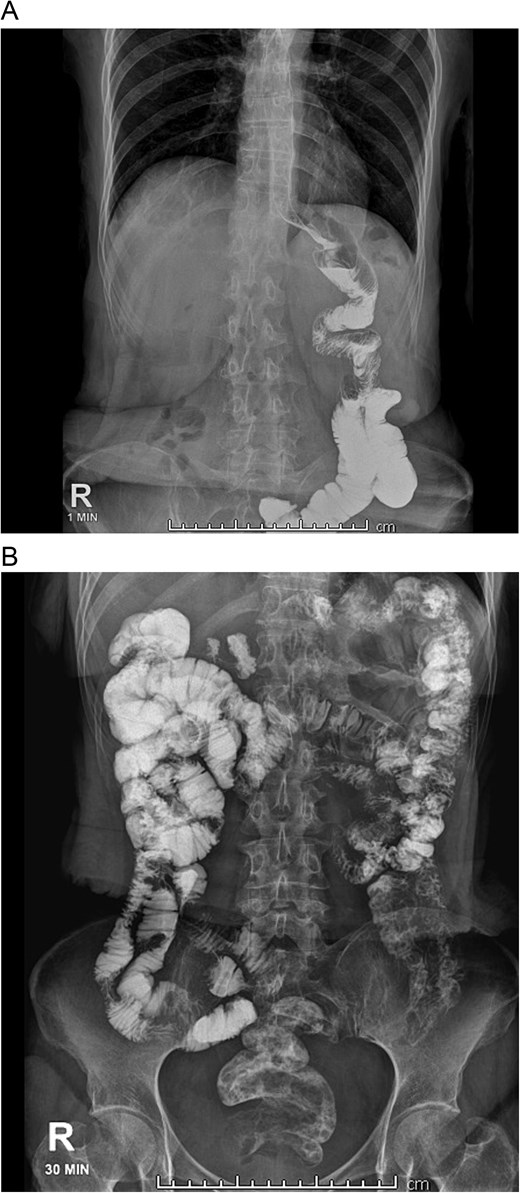

On admission, she was skinny and had bilateral edema in her extremities. Laboratory analyses showed prolonged TP and TTP (20.1 and 57.6 s), anemia (Hb: 7 mg/dl), elevated AST, ALT, GGT, and hypoproteinemia (total proteins: 3 g/dl; albumin: 1.7 g/dl). She was admitted and an endoscopy showed erythematous gastritis in an otherwise standard gastric pouch. The alimentary limb measured 80 cm and appeared normal. An abdominal computed tomography was also done, yet no masses or lymph nodes were found afterward. A bowel transit time test was also performed, which revealed that the contrast reached the anus in <30 minutes (Fig. 1A and B). A quantitative fecal fat test also revealed 9 g/24 h. With these findings, severe malnutrition due to malabsorption after an RYGB was diagnosed.

A: Bowel transit time, the complete alimentary limb and the jejunojejunal anastomosis are seen. B: Bowel transit time, in 30 minutes, it reaches the colon and anus.